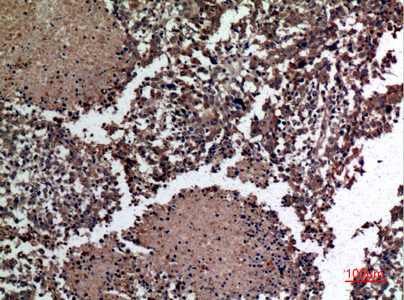

Immunohistochemistry analysis of paraffin-embedded Human lungcancer using HspBAP1 antibody.High-pressure and temperature Sodium Citrate pH 6.0 was used for antigen retrieval. |